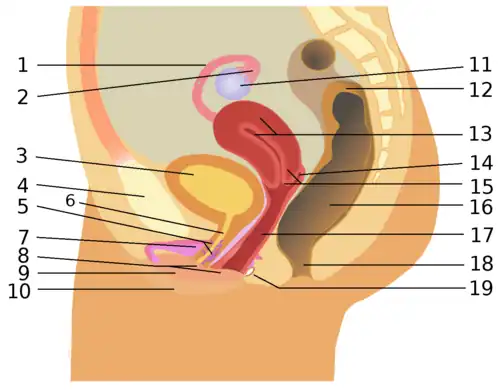

1. eileider, 2. fimbriae, 3. blaas, 4. schaambeen, 5. G-plek, 6. urinebuis, 7. clitoris, 8. vestibulum vaginae, 9. binnenste schaamlippen, 10. buitenste schaamlippen, 11. eierstok, 12. dikke darm, 13. baarmoeder, 14. fornix uteri, 15. baarmoederhals, 16. endeldarm, 17. vagina, 18. anus, 19. klier van Bartholin